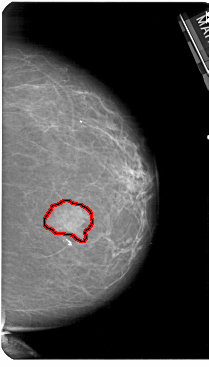

A_1182_1.LEFT_MLO

LEFT_MLO LINES 5491 PIXELS_PER_LINE 3511 BITS_PER_PIXEL 12 RESOLUTION 43.5 NON_OVERLAY

FILE: A_1182_1.RIGHT_MLO.OVERLAY

TOTAL_ABNORMALITIES 1

ABNORMALITY 1

LESION_TYPE MASS SHAPE IRREGULAR MARGINS ILL_DEFINED

ASSESSMENT 4

SUBTLETY 5

PATHOLOGY MALIGNANT

TOTAL_OUTLINES 1

BOUNDARY